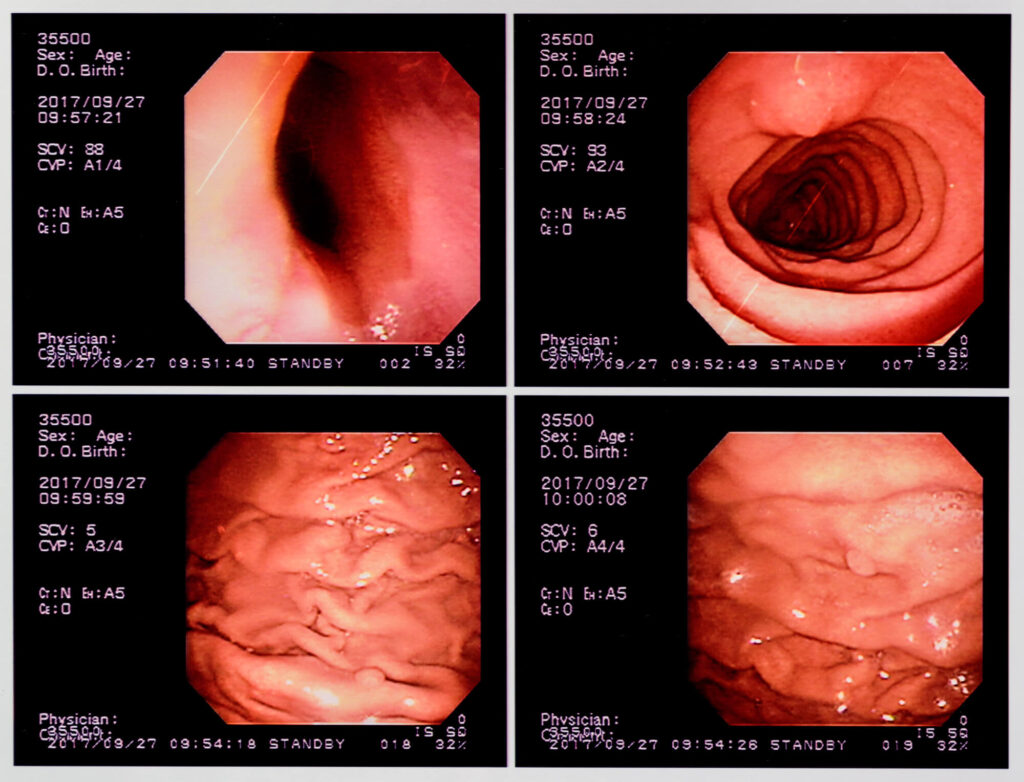

一方、胃カメラは口や鼻から内視鏡を挿入し、食道から胃、十二指腸の粘膜を直接観察できます。粘膜の色調や小さな凹凸の変化も確認できるため、早期の胃がんや微細な異常の発見にも適しています。

胃カメラの最大のメリットは、粘膜の色調やわずかな凹凸などの細かな変化や小さな病変も発見しやすい点です。また、検査中に病変が見つかれば、その場で組織を採取して病理検査(生検)もおこなえます。